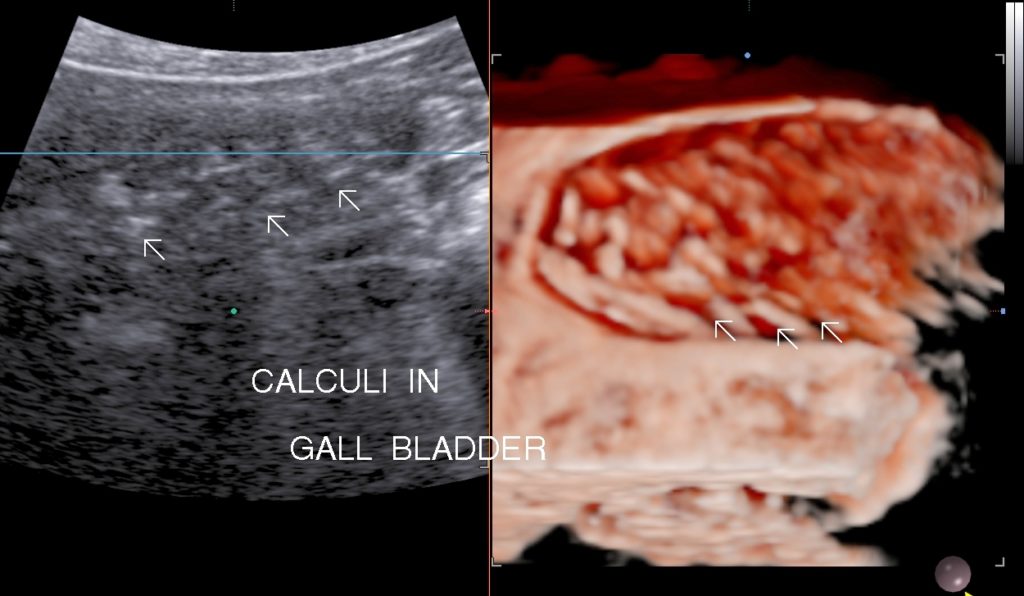

• Cholelithiasis: Presence of calculus/ calculi in gall bladder with normal wall thickness is known as cholelithiasis.

• Symptoms: Symptoms are right upper abdominal pain, dyspepsia, fullness of abdomen,bloating or may be asymptomatic. Impaction of calculi at neck or cystic duct leads to acute calculus cholecystitis. Passage of calculi in Common bile duct may lead to biliary colic , surgical jaundice & acute pancreatitis.

• Findings: Shows presence of calculi in gall bladder/ common bile duct, its mobility & complications.

• Solitary Calculi:

• Multiple Calculi